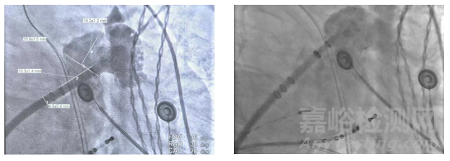

左心耳解剖:術(shù)中DSA 左心耳造影顯示,患者心耳形態(tài)為 “菜花狀雙分葉”,且存在 “縮口大 POUCH”(心耳開(kāi)口直徑 24mm,內(nèi)部腔室深度 25mm)—— 這類形態(tài)的風(fēng)險(xiǎn)在于傳統(tǒng)封堵器易出現(xiàn) “錨定不牢”(開(kāi)口窄導(dǎo)致器械固定差)或 “內(nèi)部漏血”(腔室大導(dǎo)致覆蓋不全)。

2. 手術(shù)操作過(guò)程

器械選擇:團(tuán)隊(duì)結(jié)合心耳口徑與深度,選用31mm 規(guī)格 WATCHMAN FLX Pro—— 該尺寸可確保封堵器完全覆蓋雙分葉開(kāi)口,同時(shí)避免過(guò)度壓縮導(dǎo)致器械變形。

定位與釋放:通過(guò)3 個(gè) RO Marker 實(shí)時(shí)調(diào)整器械位置,確認(rèn)封堵器與心耳開(kāi)口同軸對(duì)齊后緩慢釋放;術(shù)后經(jīng) TEE 與 DSA 雙重評(píng)估,封堵器壓縮比為 15%(理想范圍 10%-20%),無(wú)瓣周漏,符合 PASS 原則。

全球首款,波科涂層左心耳封堵器獲批上市

▲術(shù)前左心耳造影(左);封堵器展開(kāi)后TEE影像(右)

3. 術(shù)后專家反饋

周達(dá)新教授在術(shù)后訪談中表示:“這款封堵器的 PVDF-HFP 涂層能有效降低器械相關(guān)血栓風(fēng)險(xiǎn),對(duì)這類高出血風(fēng)險(xiǎn)患者,術(shù)后抗凝方案或可從‘雙聯(lián)抗血小板(DAPT)+ 抗凝’簡(jiǎn)化為‘短期 DAPT’,后續(xù)需通過(guò)隨訪驗(yàn)證這一假設(shè)。同時(shí),其對(duì)雙分葉大 POUCH 心耳的適配性,也為復(fù)雜解剖患者提供了新選擇。”